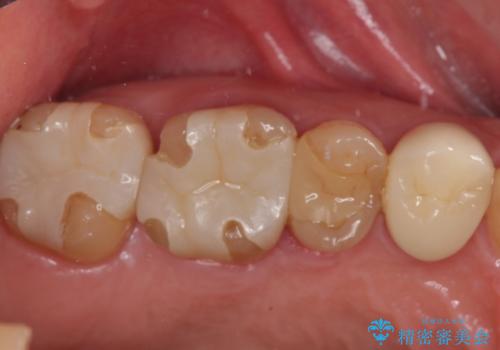

- 食事中に歯が欠けてしまった事を主訴に来院された患者様です。

小臼歯が広範囲に欠けてしまっています。

部分的な詰め物では再びかけてしまうリスクが高いため、オールセラミッククランにて補綴治療をすることとしました。

精度の高い被せものは二次う蝕のリスクが低いです。